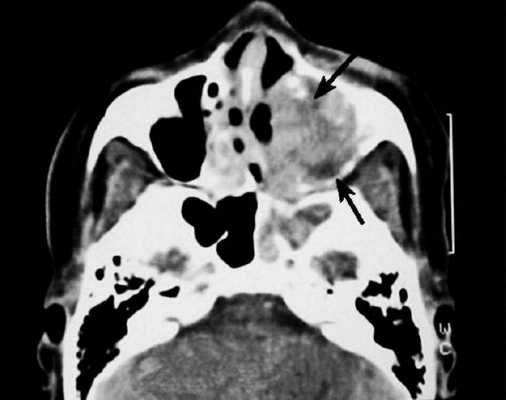

На снимке концентрическая воспалительная гипертрофия (указана стрелками) слизистой оболочки гайморовых пазух

Компьютерную томографию применяют для изучения строения костной ткани и выявления патологической жидкости в синусах носа. Исследование пазух на магнитном аппарате дает информацию о состоянии слизистых оболочек, отражает наличие новообразований. Отталкиваясь от того, что показывает МРТ пазух носа, врач может составить для пациента прогноз и назначить лечение. Процедура безопасна и высокоинформативна.